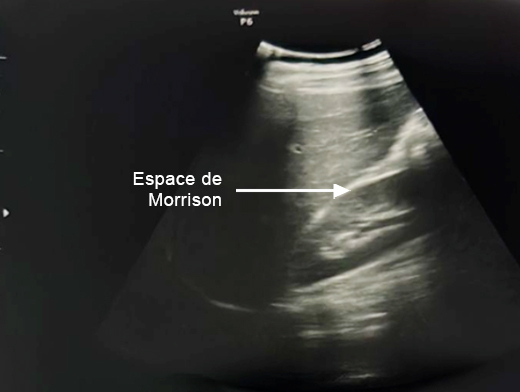

Mme G. est finalement césarisée sous anesthésie générale sans complication. Lors de l’hystérotomie, le liquide amniotique est sanglant avec de nombreux caillots. Les pertes sanguines sont estimées à 1 500 mL. L’équipe d’anesthésie a administré en peropératoire un culot de globules rouges et un plasma frais congelé (PFC), ainsi que de l’acide tranexamique. L’utérus est tonique en fin d’intervention. Au cours de la surveillance en salle de surveillance post-interventionnelle (SSPI), à quatre heures postopératoires, Mme G. a une barre épigastrique résistante aux antalgiques de palier 3. Les constantes sont les suivantes : pression artérielle = 190/110 mmHg ; fréquence cardiaque = 120 bpm ; saturation en oxygène = 99 % en air ambiant. Compte tenu de la tachycardie, vous réalisez une échographie transabdominale dont les images sont les suivantes. Figure 2a (Rodolphe Matias de Sousa, La Revue du Praticien)Figure 2b (Rodolphe Matias de Sousa, La Revue du Praticien)Figure 2c (Rodolphe Matias de Sousa, La Revue du Praticien) Vous décidez d’avancer le prochain bilan biologique et récupérez les résultats suivants : hémoglobine = 8,7 g/dL ; plaquettes = 40 G/L ; TP = 65 % ; TCA = 1,02 ; fibrinogène = 2 g/L ; haptoglobine indosable ; ASAT = 260 UI/L ; ALAT = 240 UI/L.

Concernant l’hématome sous-capsulaire du foie : Tableau 3 (Rodolphe Matias de Sousa, La Revue du Praticien) Concernant l’échographie transabdominale à la recherche d’un hémopéritoine :on regarde deux espaces, le cul-de-sac de Douglas entre l’utérus et le rectum, et l’espace de Morrison entre le foie et le rein. Figure 3a (Rodolphe Matias de Sousa, La Revue du Praticien)Figure 3b (Rodolphe Matias de Sousa, La Revue du Praticien)Figure 3c (Rodolphe Matias de Sousa, La Revue du Praticien) Pour rappel, concernant l’échographie en gynécologie : Figure 4a (Rodolphe Matias de Sousa, La Revue du Praticien)Figure 4b (Rodolphe Matias de Sousa, La Revue du Praticien)Figure 4c (Rodolphe Matias de Sousa, La Revue du Praticien)Figure 4d (Rodolphe Matias de Sousa, La Revue du Praticien)Figure 4e (Rodolphe Matias de Sousa, La Revue du Praticien)Figure 4f (Rodolphe Matias de Sousa, La Revue du Praticien)Figure 4g (Rodolphe Matias de Sousa, La Revue du Praticien)Figure 4h (Rodolphe Matias de Sousa, La Revue du Praticien)Figure 4i (Rodolphe Matias de Sousa, La Revue du Praticien)